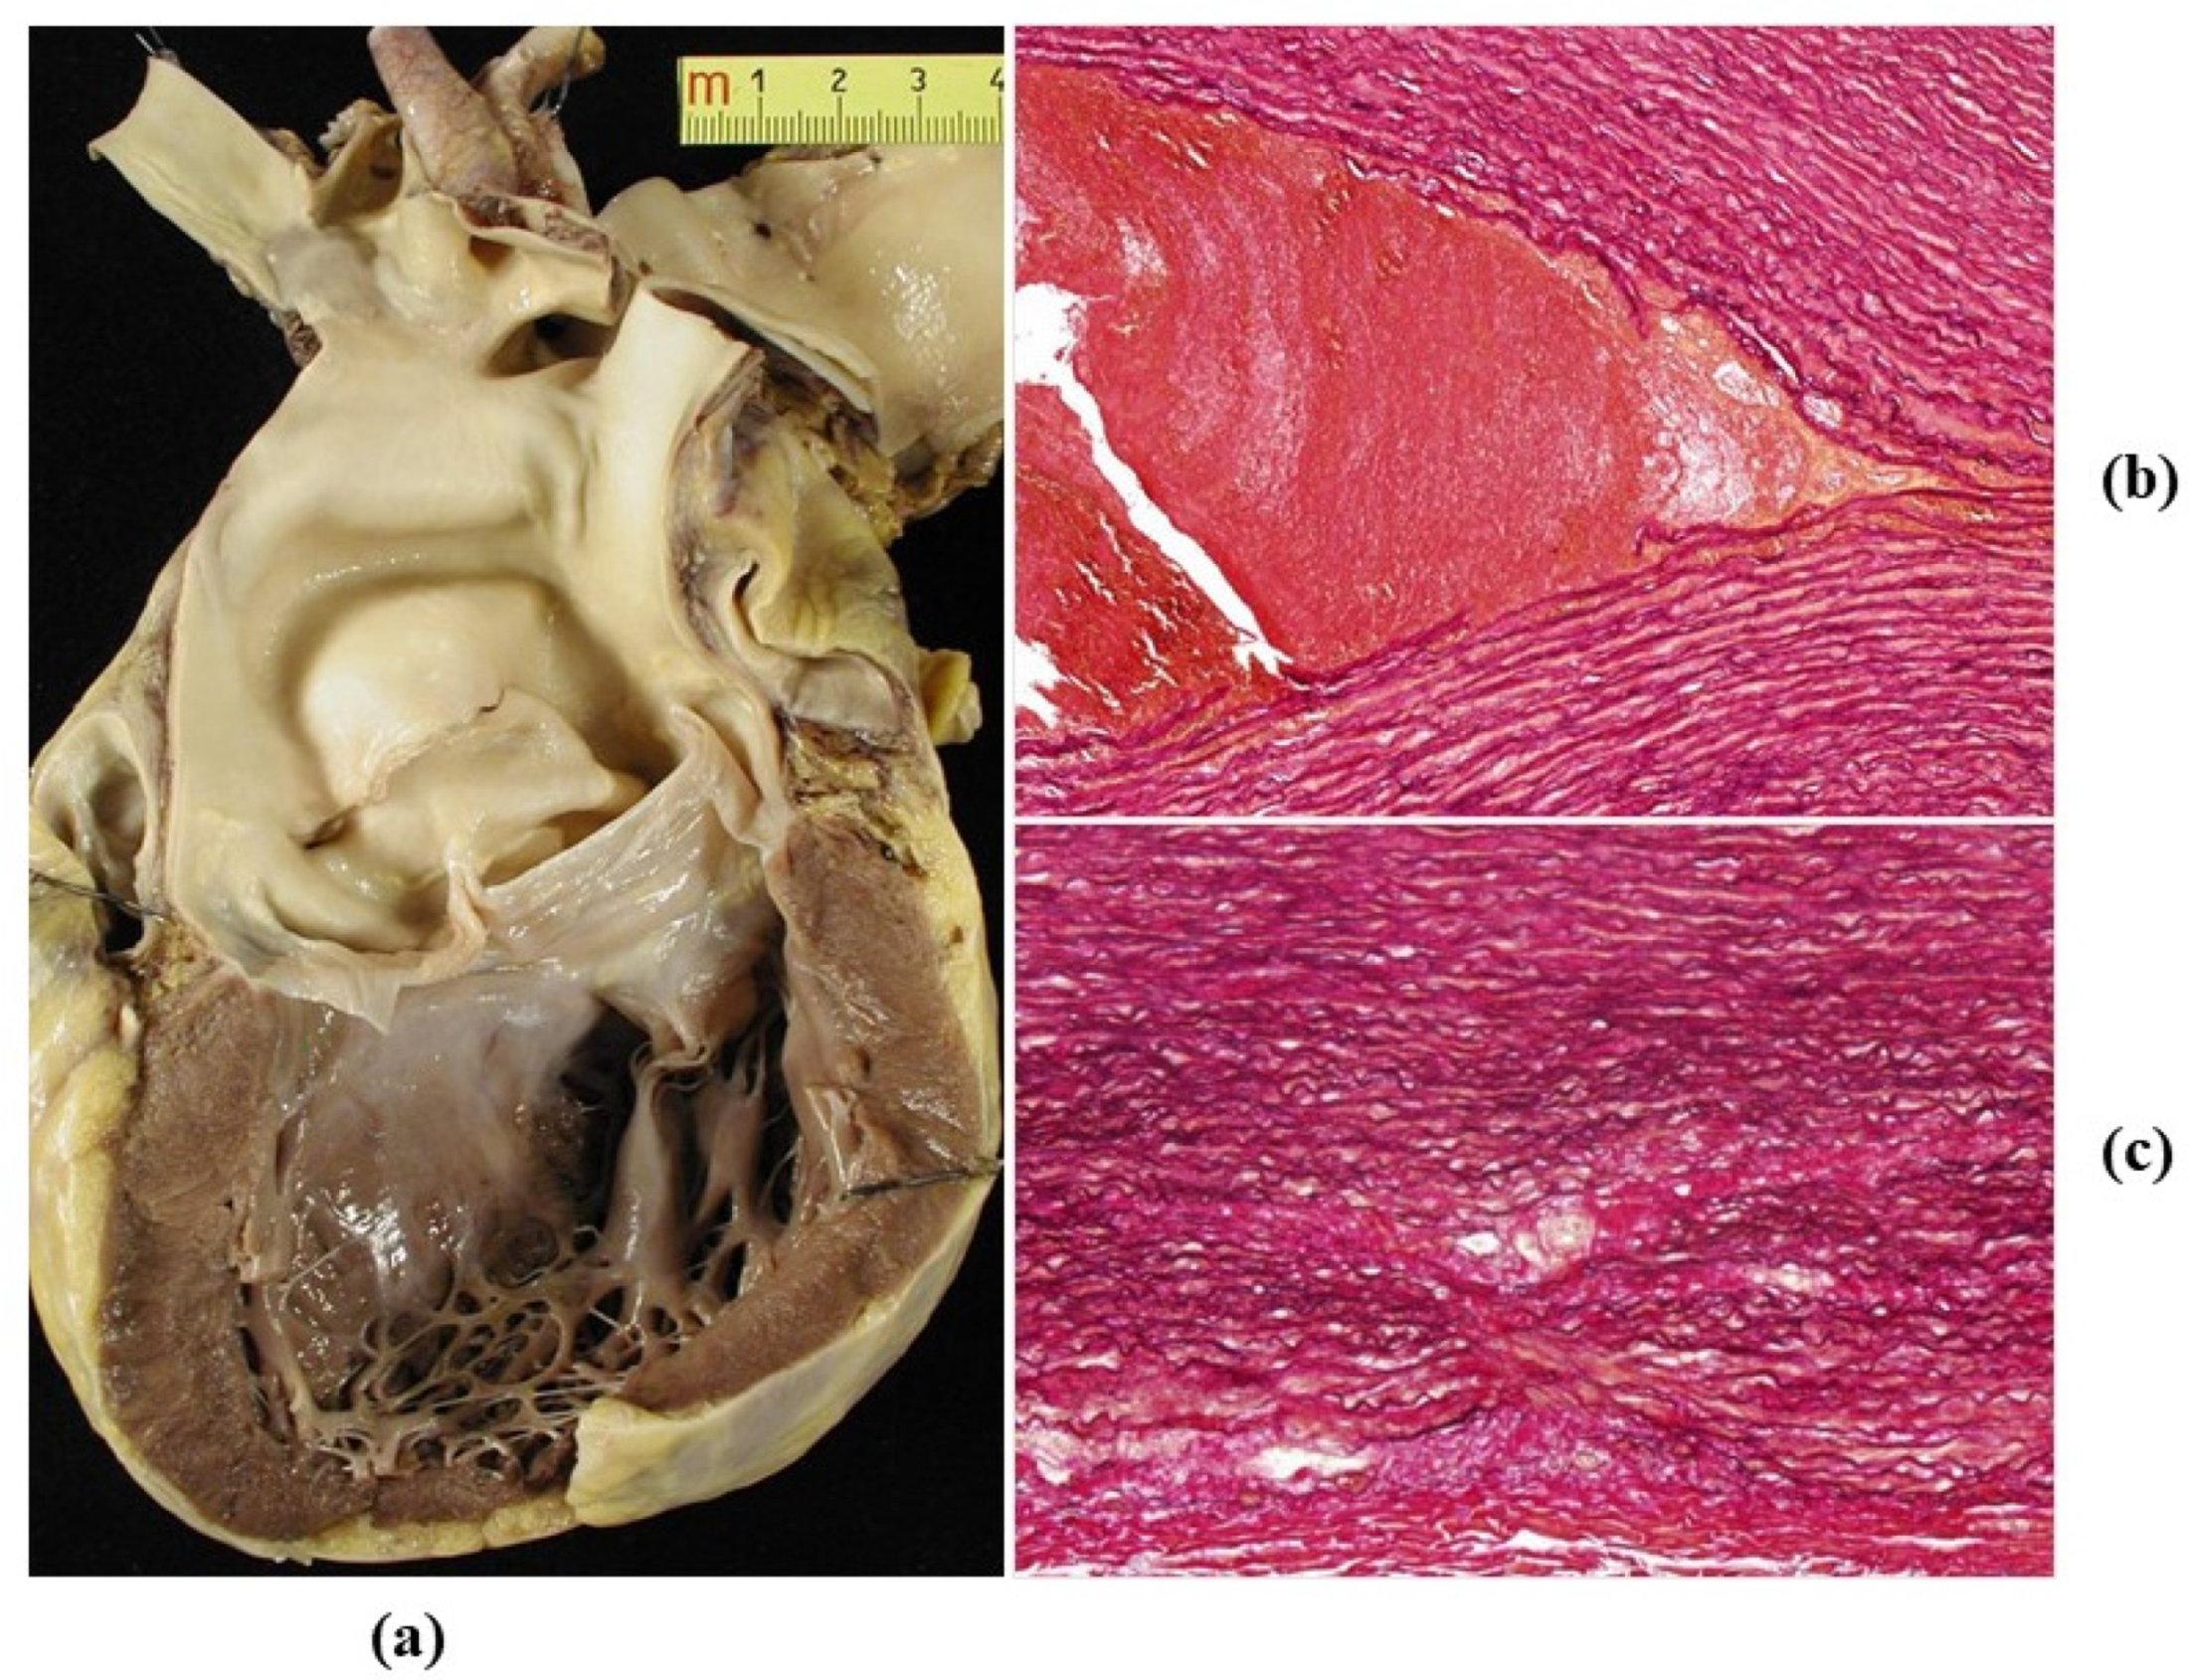

- Decellularization in unimplanted allografts appeared complete, both in the lamellar units of the tunica media and valvular interstitium with disappearance of endothelial lining (Figure 31);

- Cellular repopulation was observed in the outer part of implanted homograft wall by novel smooth muscle cells in the lamellar units (Figure 32a,b) and in the intima with a novel myointimal layer; this layer was noticed also in small animals such as rodents [68]. Novel endothelial cells appeared to line both the aortic wall intima and inflow/outflow at the cusp surface, as well as vasa vasorum, and valve spongiosa appeared repopulated by interstitial cells (Figure 32c,d);